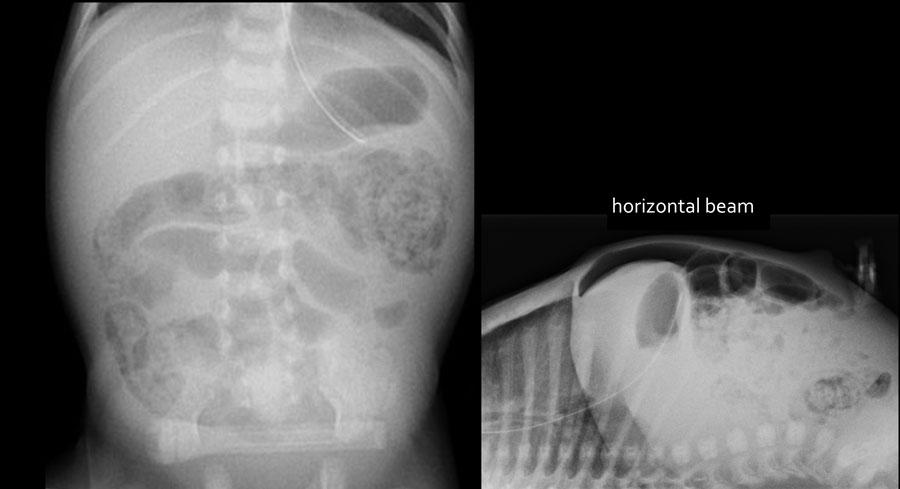

Các hình ảnh cho thấy một trường hợp điển hình của viêm ruột hoại tử với khí trong thành ruột.

Trên hình chụp tia ngang, không có dấu hiệu khí tự do trong ổ bụng.

Các dấu hiệu bao gồm:

- Nhiều quai ruột non giãn

- Khí trong thành ruột (Pneumatosis intestinalis).

- Tràn khí ổ bụng (Pneumoperitoneum).

Chẩn đoán:

Viêm ruột hoại tử (NEC) có thủng ruột.